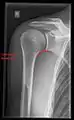

- Y-projection

The lateral contour of the shoulder should be positioned in front of the film in a way that the longitudinal axis of the scapula continues parallel to the path of the rays. This method reveals:[24]

- The horizontal centralization of the humerus head and socket

- The osseous margins of the coraco-acromial arch and hence the supraspinatus outlet canal

- The shape of the acromion

This projection has a low tolerance for errors and, accordingly, needs proper execution.[24] The Y-projection can be traced back to Wijnblath’s 1933 published cavitas-en-face projection.[25]

Y-projection conventional radiography